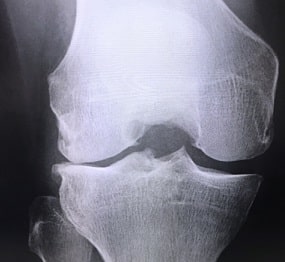

膝の画像検査では、主にX線撮影が行われます。X線写真にはっきりと映るのは骨の状態のみです。

正常な膝関節なら、大腿骨と脛骨の骨頭がそれぞれ厚さ3から4ミリの関節で覆われ、骨と骨の間は厚さ約6から8ミリの隙間が移ります。

変形性関節症の場合、関節軟骨がすり減るため、隙間が狭くなったり、変形したりして移ります。

関節軟骨が減ると、骨と骨が直接触れるので、骨棘と言う尖った小さな角のような骨や、骨堤という堤防のような盛り上がりができます。

また、骨と骨のぶつかる部分が白く映った場合は、骨が硬くなってしまう骨硬化症の疑いがもたれます。